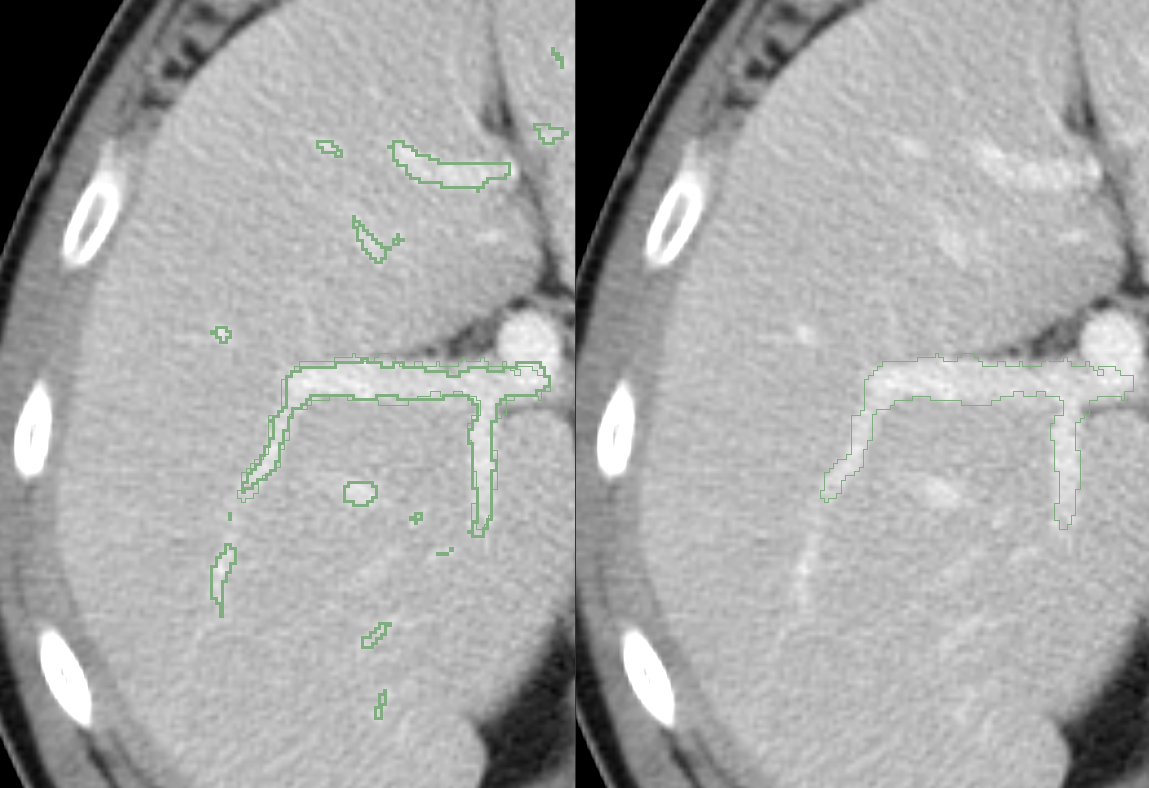

1. 标注目标转变

从“器官轮廓”转向:

肝动脉 / 门静脉 / 肝静脉的树状结构识别

标注重点变为:

- 连续性

- 分支完整性

- 空间走行

(1)Threshold(初筛)

- 用于快速提取高密度血管结构

- 优点:效率高、边界清晰

- 局限:对小血管和低对比区域不稳定

👉 当前认知修正:

Threshold 仅作为“辅助初筛工具”,不能作为最终标注依据